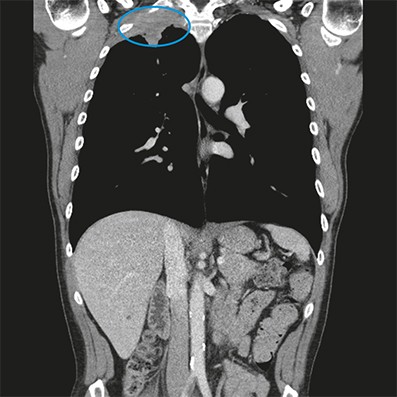

Hoewel de patiënt telkens na een behandeling minder pijn heeft, komen de klachten ook steeds weer terug, nu ook in de nacht. Hij vertelt dat hij zich langzaamaan zorgen maakt over longkanker, waaraan zijn vader op 53-jarige leeftijd overleed. De patiënt rookt en heeft dertig pakjaren. Hierop laat de huisarts-in-opleiding, inmiddels twee maanden na het eerste spreekuurbezoek, bloedonderzoek en een X-thorax verrichten. De bezinking is 40 mm/uur en de röntgenfoto toont opvallende, rechtszijdige toppleuraverbreding die kan wijzen op een longtoptumor. Aanvullende beeldvorming door de longarts bevestigt de aanwezigheid van een ruimte-innemend proces van de longtop, met ingroei in de intercostaalruimtes van rib 1 en 2 en partiële destructie van deze ribben [figuur]. Pathologisch onderzoek laat een plaveiselcelcarcinoom zien, cT3N0M0. De patiënt start met concurrente chemoradiatie. In de toekomst zal en-bloc lobectomie van de rechterbovenkwab volgen.